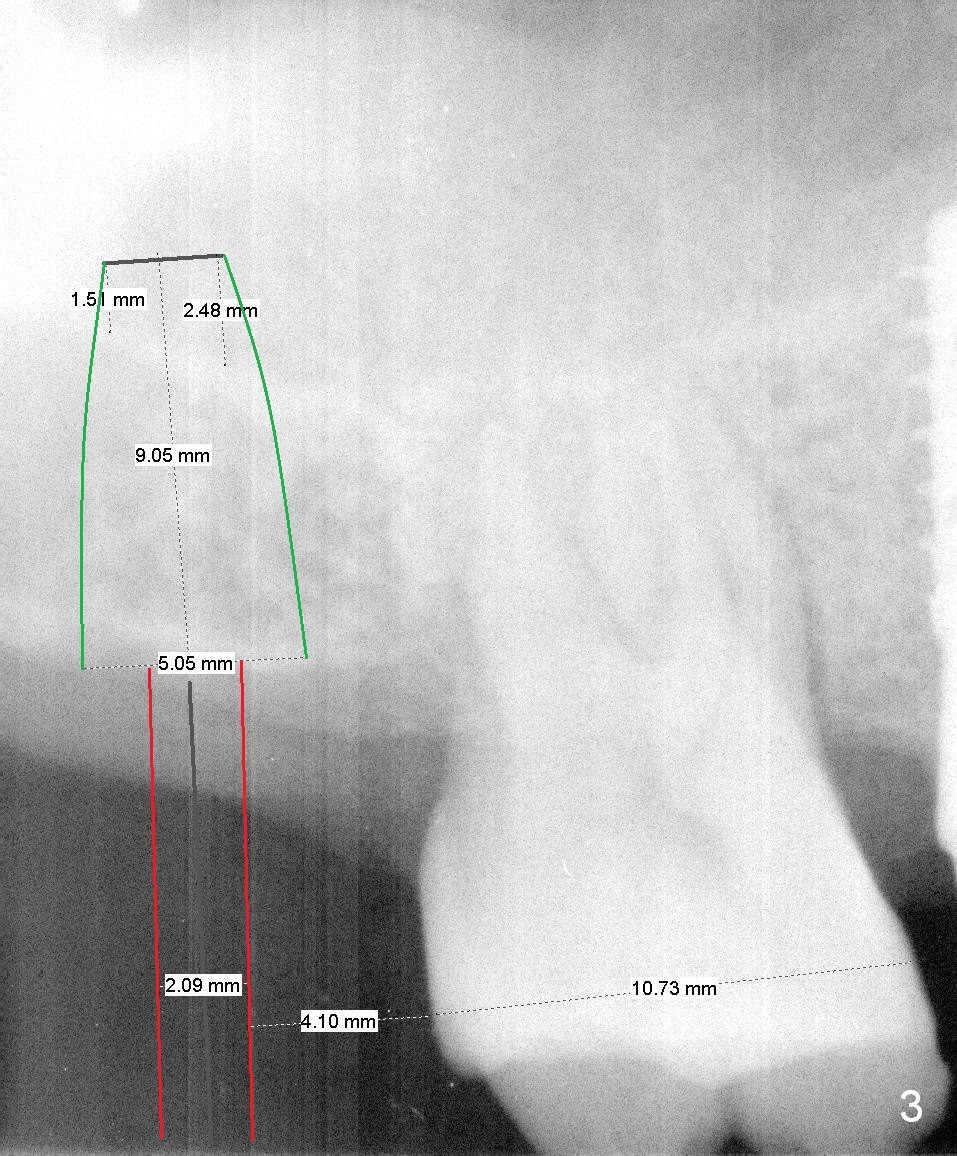

There is a tendency to drift osteotomy distally at the upper 2nd molar area when the 3rd molar is missing. Without a surgical stent, an implant spacer should be used constantly from the beginning (pilot drill) to the end (implant placement, Fig.3) for the site of #2 of the 47-year-old man (Fig.2). The tooth was extracted because of periodontitis and bruxism (Fig.1 (taken 5 years earlier)). Please measure the diameter of the handle of every instrument, including drill, expander and implant driver in advance (Fig.3 red lines). The center of the handle should be 5 mm from the distal surface of the 1st molar. If the diameter of the handle is 2 mm, the implant spacer is set to be 4 mm (Fig.3). For convenience of insertion (the edge of the spacer is wider than the center), use the 3.5 mm one. Take PA as early as possible and change position with a Lindamann bur accordingly. Prepare Magic Sinus Kit and separate IBS implant driver (in a pouch, not from a cassette).